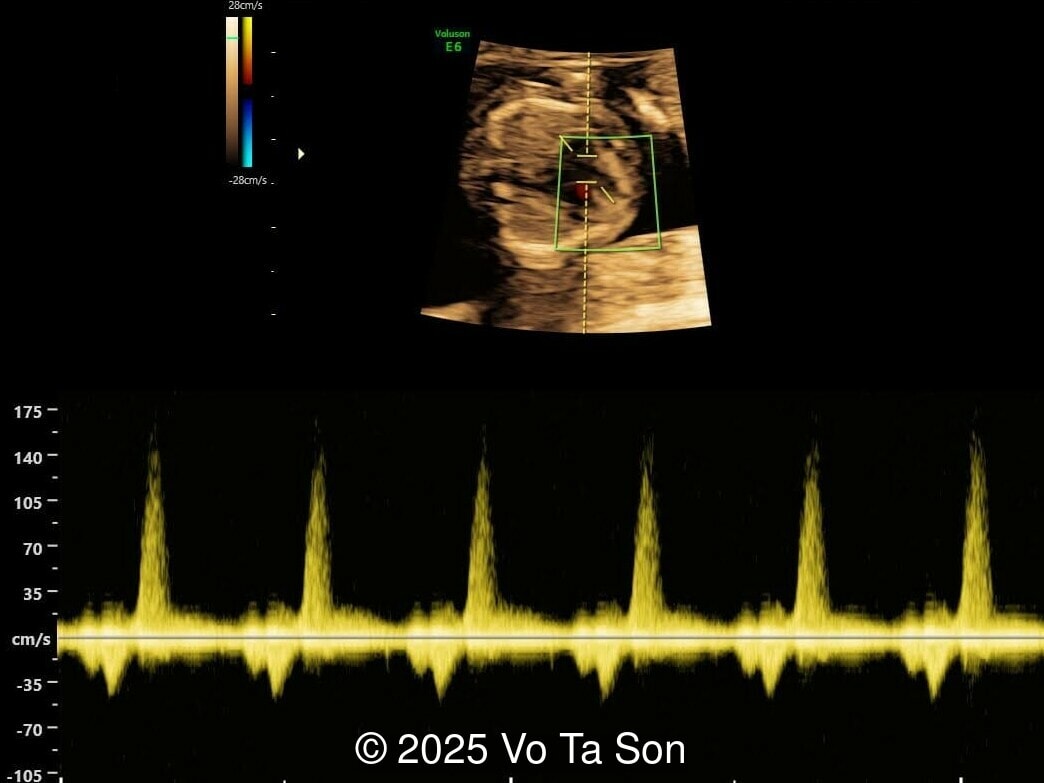

A woman underwent routine prenatal screening at 13 weeks. The non-invasive prenatal test (NIPT) showed low risk for common aneuploidies including trisomy 21, 18, and 13. However, first-trimester anomaly scan revealed multiple fetal anomalies.

We present a case of Triploidy with a 69,XXY chromosomal complement and open spina bifida in the first trimester.

Our imaging revealed the following significant fetal abnormalities:

• Ventricular septal defect (VSD)

• Tricuspid valve regurgitation